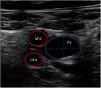

Vascular ultrasound allows us to measure vessel diameter to select the optimum cannula size (Fig. 1). The following formula is used for this purpose: cannula caliber (French (Fr)) = 3 × vessel diameter (mm). The largest cannula size should be used for both drainage and return, in order to ensure the greatest flow possible. Ultrasound-guided vascular puncture increases the safety and success rate at the first attempt, reducing the risk of local complications (arterial cannulation, cannulation of the saphenofemoral junction or transfixation of the inguinal ligament).20,11